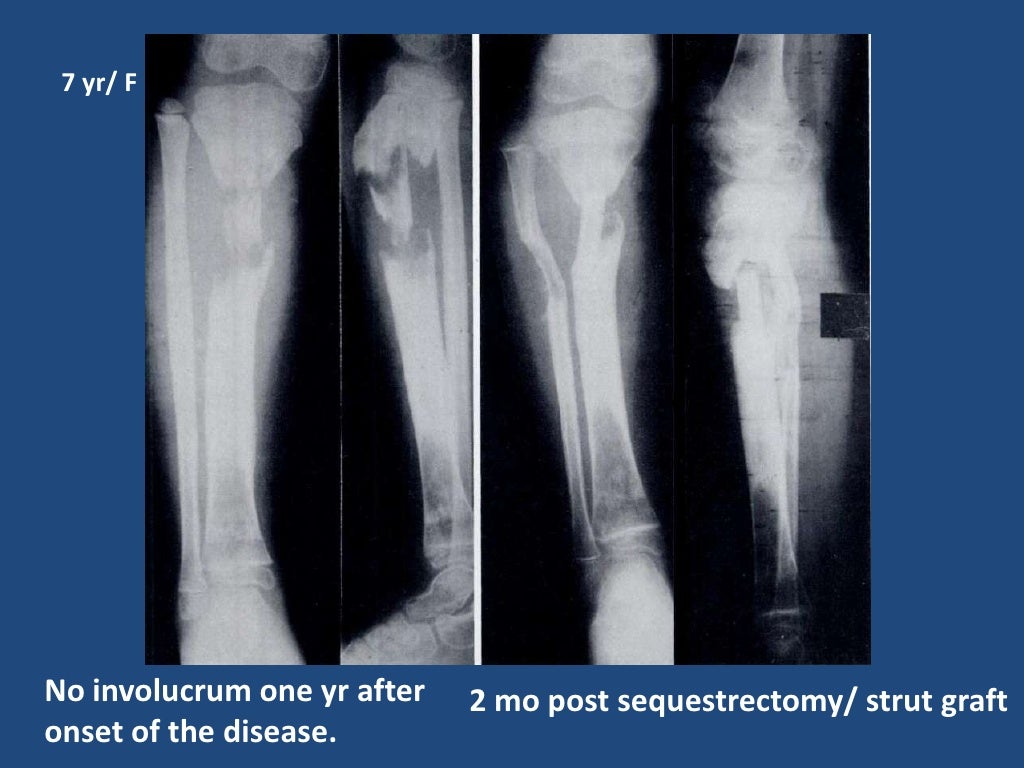

From www.slideshare.net

Chronic Osteomyelitis In Children Osteomyelitis Symptoms In Toddlers Swelling, warmth and redness over the area of the infection; Have swelling, redness, warmth or pain in the area. Not want to use the affected. It's usually caused by a bacterial infection. Acute osteomyelitis (ao) and acute septic arthritis (sa) should be considered in all children who present with pain involving a bone. What are the symptoms of osteomyelitis? Signs. Osteomyelitis Symptoms In Toddlers.

Chronic Osteomyelitis In Children Osteomyelitis Symptoms In Toddlers The following are the most common symptoms of osteomyelitis. Signs and symptoms of osteomyelitis include: What are the symptoms of osteomyelitis? Call us to schedule 513. Not want to use the affected. Osteomyelitis is the medical term for inflammation in a bone. Acute osteomyelitis (ao) and acute septic arthritis (sa) should be considered in all children who present with pain. Osteomyelitis Symptoms In Toddlers.

Chronic Osteomyelitis In Children Osteomyelitis Symptoms In Toddlers Not want to use the affected. The following are the most common symptoms of osteomyelitis. It's usually caused by a bacterial infection. Signs and symptoms of osteomyelitis. Call us to schedule 513. Have swelling, redness, warmth or pain in the area. Osteomyelitis is the medical term for inflammation in a bone. Acute osteomyelitis (ao) and acute septic arthritis (sa) should. Osteomyelitis Symptoms In Toddlers.

Chronic Osteomyelitis In Children Osteomyelitis Symptoms In Toddlers Acute osteomyelitis (ao) and acute septic arthritis (sa) should be considered in all children who present with pain involving a bone. Signs and symptoms of osteomyelitis. Have swelling, redness, warmth or pain in the area. The following are the most common symptoms of osteomyelitis. Swelling, warmth and redness over the area of the infection; What are the symptoms of osteomyelitis?. Osteomyelitis Symptoms In Toddlers.

Chronic Osteomyelitis In Children Osteomyelitis Symptoms In Toddlers Not want to use the affected. Signs and symptoms of osteomyelitis include: Call us to schedule 513. Swelling, warmth and redness over the area of the infection; It's usually caused by a bacterial infection. Osteomyelitis is the medical term for inflammation in a bone. Signs and symptoms of osteomyelitis. The following are the most common symptoms of osteomyelitis. What are. Osteomyelitis Symptoms In Toddlers.